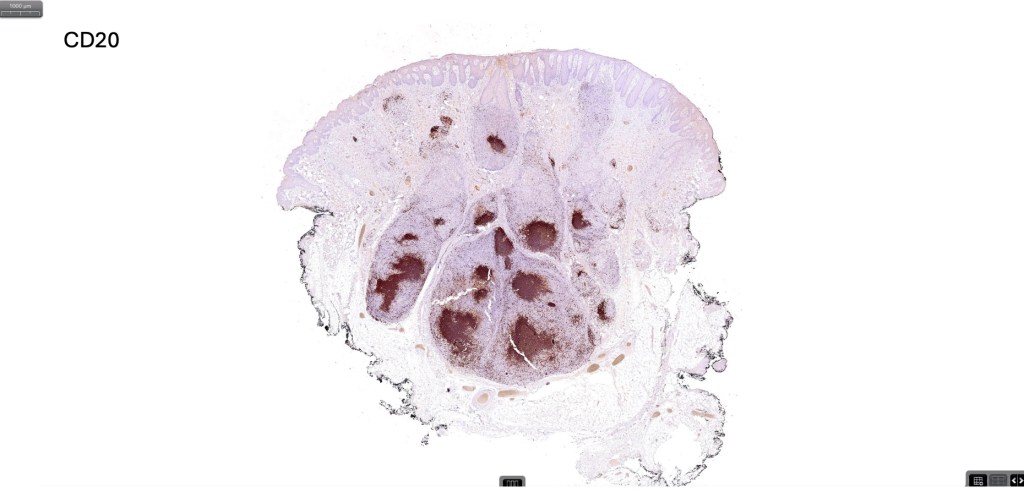

Histological features

•Follicular infiltration by atypical lymphocytes & Sézary cells